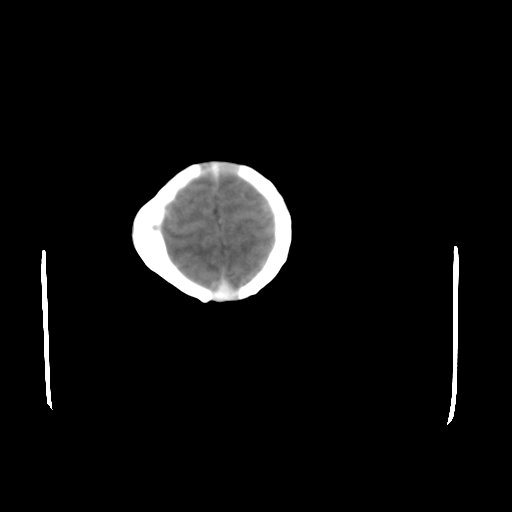

男,12天,自然分娩,其母发现右顶部头皮包块逐渐增大。

右顶部头皮血肿

右顶部头颅血肿(骨膜下血肿)

右顶骨呈膨胀性改变,骨纤维结构不良?

右顶部头皮血肿,可能是产道挤压所致。以后会慢慢恢复。

鉴别:骨膜下血肿,一般为产伤,应用产钳之类的吧

疑问:患儿脑白质密度比较低,基底节区密度比较高,类似于“双圈征”脑沟密度也偏高。该婴儿可有别的异常吗?反射正常吗?评分能达到5分吗?如果正常,就随诊观察吧。不正常要考虑到缺血缺氧性脑病。